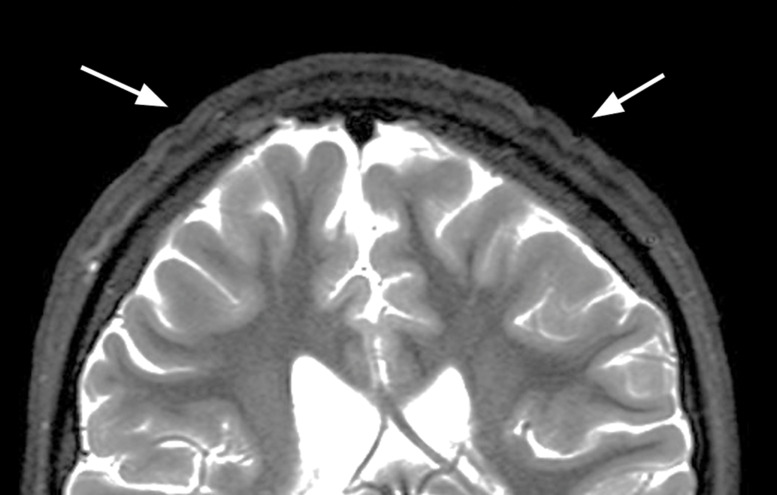

Cutis Verticis Gyrata: A Secondary Form of a Rare Skin Condition Caused by Growth Hormone Therapy.

Teaching point: To recognize cutis verticis gyrata on MRI and raise awareness of growth hormone therapy as a possible cause.